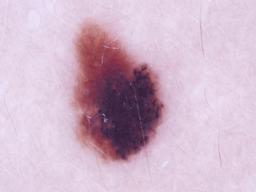

{

"age_approx": 70,

"anatom_site_general": "posterior torso",

"concomitant_biopsy": true,

"diagnosis_1": "Malignant",

"diagnosis_2": "Malignant melanocytic proliferations (Melanoma)",

"diagnosis_3": "Melanoma, NOS",

"diagnosis_confirm_type": "histopathology",

"image_type": "dermoscopic",

"lesion_id": "IL_3061699",

"melanocytic": true,

"sex": "male"

}